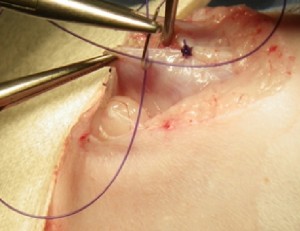

症例:年齢不明 雄 和猫

主訴:腹部より内部臓器が脱出している猫を保護したと来院した。

保護猫であるため齊ヘルニアによる便秘や嘔吐などの症状の有無、腹部内容の脱出原因は不明であったが何らかの症状がでる、感染症になる可能性や周囲の皮膚や組織の壊死が起こる可能性があったため齊ヘルニアの整復手術を行った。

経過:ヘルニアの整復は行われたため、便秘等の症状や感染症は見られず、現在は健康に過ごしている。